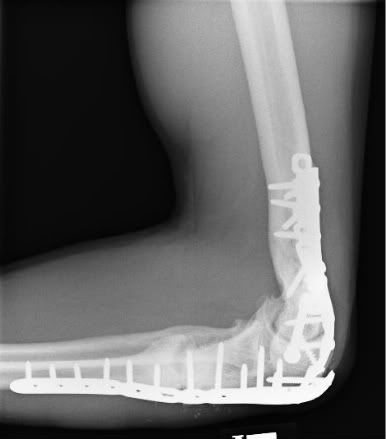

Before going under knife on July 20th, most would tease me with comparisons to Marvel's Wolverine as a result of the comical amount of surgical hardware I have holding my frame together.

Hunky superhero jokes aside, I've been living with several left ulna "non-unions" since 2005 resulting in "overactive bone growth" in my arm.